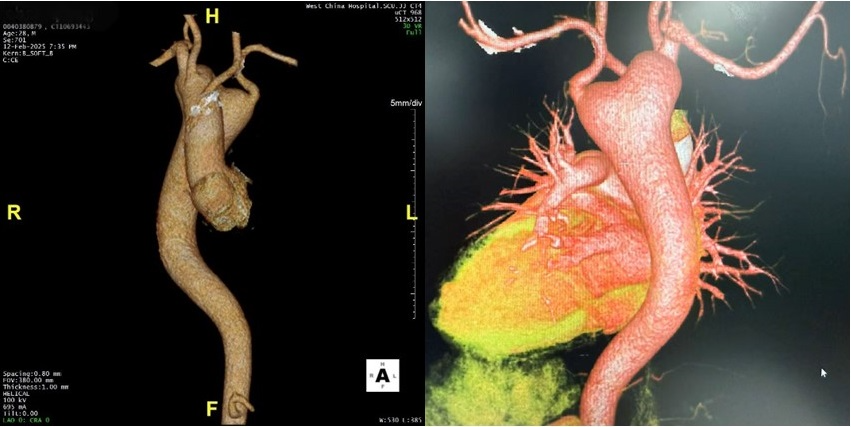

图片

术前CTA提示主动脉窦部动脉瘤、右位主动脉弓、Kommerell憩室以及降主动脉瘤/图源:受访者